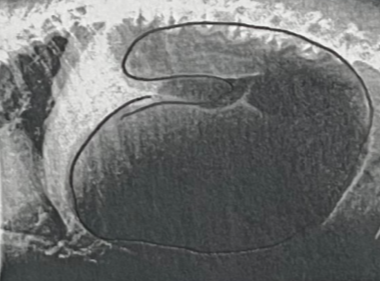

This is the dog’s radiograph, what abnormality can cause these findings

Stomach is pushing on the diaphragm due to gastric dilation and volvulus, where the stomach twists on itself